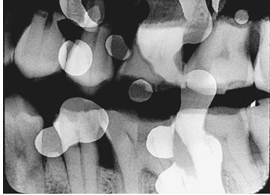

What is the problem with this OVERLAPPED FILMS X-ray?

White or dark areas appear on film where overlapped, Two films contacting each other during processing

How would you resolve this OVERLAPPED FILMS X-ray?

Separate films so that no contact takes place during processing